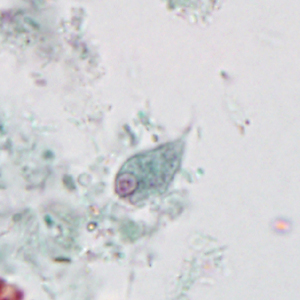

Stool specimens were collected from an asymptomatic 12-year-old boy from Myanmar as part of a refugee screening program. The stool was collected in 10% formalin and zinc PVA (Zn-PVA) and sent to the county health department for routine ova-and-parasite (O&P) examination. Figures A–D show what was observed at 1000x magnification with oil on a trichrome-stained slide made from stool preserved in Zn-PVA. The objects shown in Figures A–C measured 12-15 µm in length, on average; the object in Figure D measured 7 µm. What is your diagnosis? Based on what criteria?

Figure A